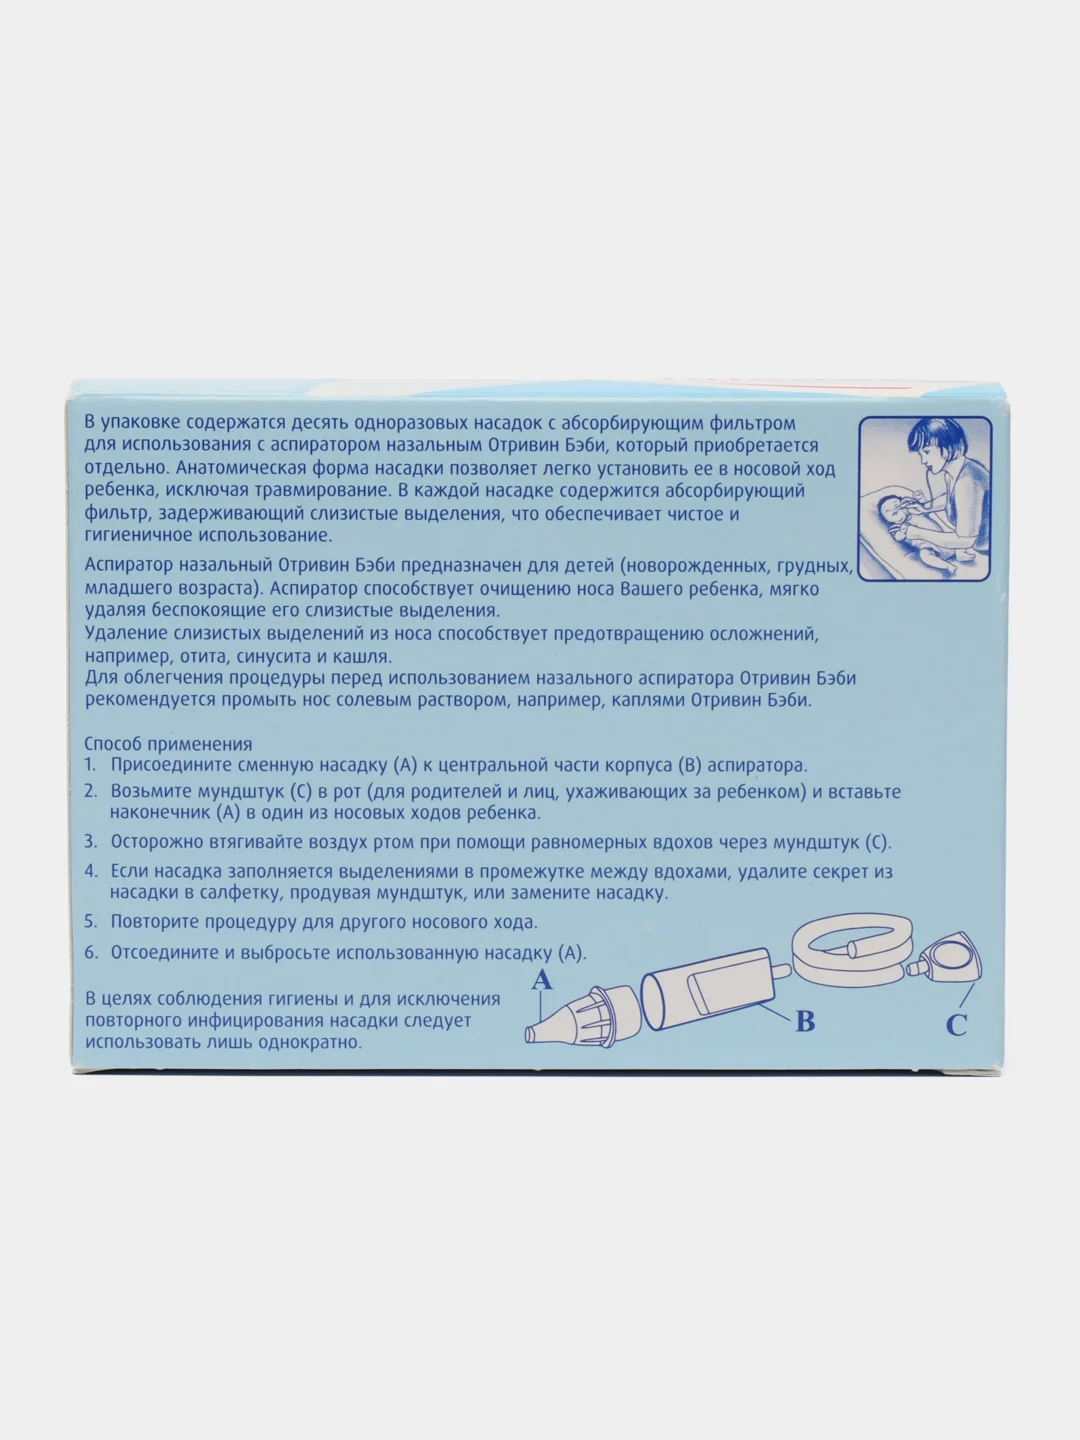

Насадки сменные для назального аспиратора Отривин Бэби.

Сменные насадки идеально подходят для носика малыша - содержат впитывающий фильтр, удерживающий слизь.Гигиеничны в применении. Во избежании повторного инфицирования использованную насадку следует выбросить.

Насадки сменные для назального аспиратора Отривин Бэби.

Сменные насадки идеально подходят для носика малыша - содержат впитывающий фильтр, удерживающий слизь.Гигиеничны в применении. Во избежании повторного инфицирования использованную насадку следует выбросить.